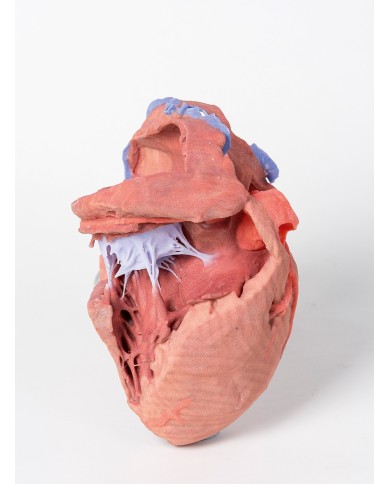

I modellini anatomici di cuore umano sono strumenti indispensabili per uno studio corretto dell'anatomia del cuore umano.

Fra i modelli di base segnaliamo il modello di cuore classico in due parti, in cui le due metà del cuore sono tenute insieme da potenti magneti.

Inoltre nella categoria sono presenti anche i modellini anatomici di cuore con bypass e con sistema di conduzione, fino ai modelli anatomici comparativi di patologie del cuore.

Per una migliore comprensione delle strutture anatomiche del cuore sono stati realizzati anche dei modelli anatomici di cuore ingrandito, si va dai piccoli ingrandimenti fino ai modelli di cuore per la formazione in aula, come il modello anatomico di cuore gigante prodotto da 3B Scientific: un modello di cuore ingrandito di ben otto volte.

Su Tuttoanatomia trovi la più vasta selezione online, certamente abbiamo il modello di cuore più adatto alle tue esigenze. I cardiologi e gli studenti acquistano i modelli anatomici di cuore umano per studiare nei minimi dettagli la struttura anatomica del cuore umano, ma anche per dare spiegazioni ai propri pazienti, per illustrare visivamente la patologia di cui sono affetti, ed il tipo di intervento che si intende eseguire durante la terapia. Le quotazioni su Tuttoanatomia sono le più convenienti del mercato e la qualità dei prodotti è davvero eccezionale, in modo da offrirti un rapporto qualità prezzo incomparabile.